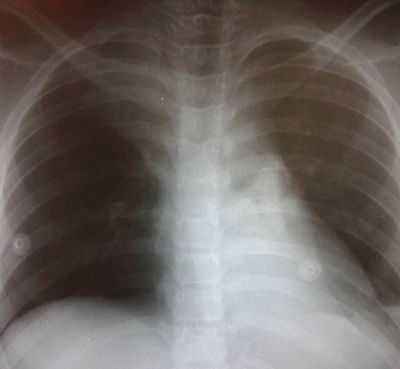

Niña de 9 años, 32 Kg APP: asma leve intermitente sin tratamiento profiláctico, sólo salbutamol en crisis. Nunca internada. Última crisis hace un año. DIA 1: comienza con tos y dificultad respiratoria progresiva, con sibilancias audibles sin estetoscopio. Consulta por guardia de emergencias de hospital dónde le realizan aerosol terapia de rescate para broncoespasmo durante 1 hora, nebulizaciones con adrenalina. Logra SpO2 = 97% pero con requerimientos de O2 por máscara con reservorio. Rx de tórax con 8 EIC bilaterales, atrapamiento aéreo y atelectasia del vértice del pulmón derecho. Laboratorio GB: 16.250 (90/7) - PCR: 2.7, Gases art: 7.35/34/55/18.5/-6.3/86%, Ionograma: 142/4.7/105/Ca:5.3 Hcto: 38, Hb: 12 Signos vitales: afebril (siempre), FR: 40 x', FC: 120 x', TA: 95/50 Al examen físico respiratorio: hipoventilación en ambos campos pulmonares, no roncus ni sibilancias, respiración en balancín, tiraje universal. ¿Cuál es su diagnóstico sindrómico?

Answer

• Síndrome de hipoventilación alveolar congénica

• Síndrome de dificultad respiratoria por patrón obstructivo

• Síndrome de dificultad respiratoria por patrón restrictivo